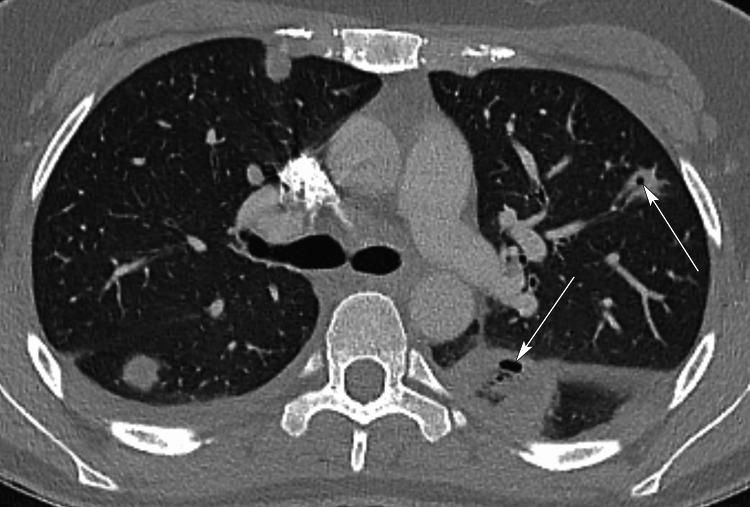

Lemierre's syndrome is a condition characterized by septicemia, with bacteremia, thrombophlebitis of the internal jugular vein (IJV), and septic embolization to distant organs following a recent upper respiratory infection (URI). an anaerobic Gram-negative rod, has been mostly implicated as the causative organism of this condition that tends to affect healthy teenagers and young adults. While once regarded as a disease of old, it has seen a resurgence in recent times, possibly due to antibiotic stewardship and current trends of reduced antibiotic use for URIs. It is important that the modern physician has a high index of suspicion, as well as the characteristic presentation of this potentially fatal illness. Current treatment guidelines are centered on the use of appropriate antibiotics, drainage of purulent collections when possible, and, in some situations, anticoagulants have been utilized. This study describes a case of a young lady who presented with symptoms of chest pain and deteriorating oxygen saturations following recent treatment for acute tonsillitis.